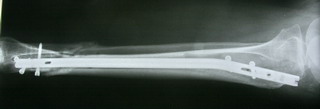

Заштифтовали 11мм реконструктивным штифтом, увы устранить деформацию

полность даже поллер винтами нам не удалось. Интрооперационно на экране ЭОпа

оан выглядела не так критически, как на контрольных снимках после операции.

Задним умом надо было отложить штифтование после репозиции в аппарате ( прав

был  А.Н.Челноков!), слишком были заняты идеей удаления отломка штифта не

оценив проблему устранения деформации. В п/операционном периоде разрешили

дозированную нагрузку на конечность.